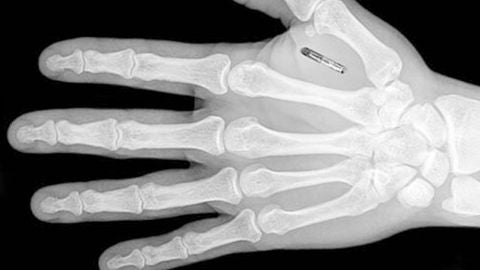

En la Tertulia zona cero de La Rosa de los vientos, Juanjo Sánchez-Oro, Josep Guijarro y Miguel Pedrero debaten sobre la profecía cumplida del Gran Hermano. Además, hablamos de la implantación de chips bajo la piel, de la investigación que analiza si realmente se ve pasar toda la vida por delante de los ojos antes de morir, de la aparición de geoglifos en el Amazonas y de la reprogramación cerebral. Por otro lado, nos acercamos al viaje de Colón y al viaje de los soldados americanos en Vietnam, donde se dice que tuvieron encuentros con extrañas criaturas.